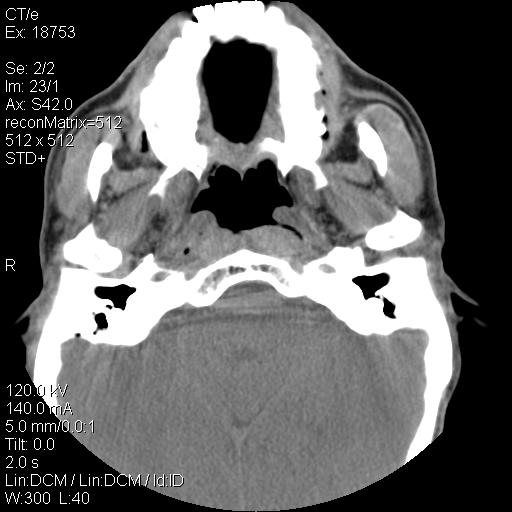

标题: CT21693:男 58岁 右侧咽部疼她2天余 PE:右侧扁桃体肿大 压痛 [打印本页]

标题: CT21693:男 58岁 右侧咽部疼她2天余 PE:右侧扁桃体肿大 压痛

喉部新生物,喉癌可能大,建议喉镜取组织活检。

喉癌可能大

右化脓性扁桃体炎症伴咽后壁脓肿形成.